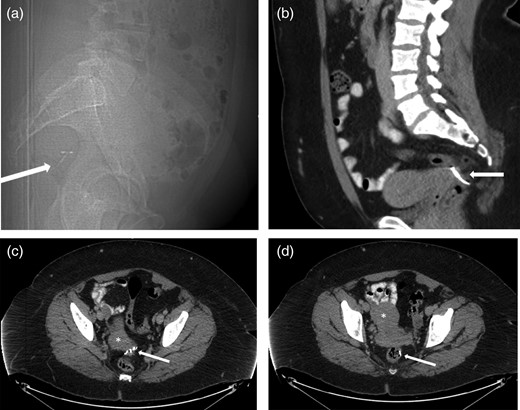

A 37-year-old woman had an IUD inserted 1 year after her only pregnancy. The patient experienced post-procedural bleeding. At her follow-up, the strings of the IUD were not visualized, which was suspicious for IUD migration. An attempt at laparoscopic retrieval was unsuccessful. A computed tomography (CT) scan showed migration of the IUD with the T-arms of the device seen posterior to the left vaginal fornix with the shaft within the lower rectum (Fig. 1). A general surgeon was subsequently consulted, and a diagnostic flexible sigmoidoscopy was performed, which demonstrated protrusion of the IUD into the rectal lumen. The patient was then referred to a colorectal specialist.

(a) Sagittal CT Scout view shows IUD (arrow) in very posterior location, probably within the rectum. (b) Sagittal contrast-enhanced CT of the pelvis showing the extra-uterine position of the contraceptive device (arrow) posterior to the uterus. (c) Axial contrast-enhanced CT of the pelvis reveals extra-uterine position of the contraceptive device arms (arrow) posterior to the cervix (*). (d) Axial contrast-enhanced CT of the pelvis showing the extra-uterine position of the stem of the contraceptive device within the rectal lumen (arrow) after perforating the uterus (*).